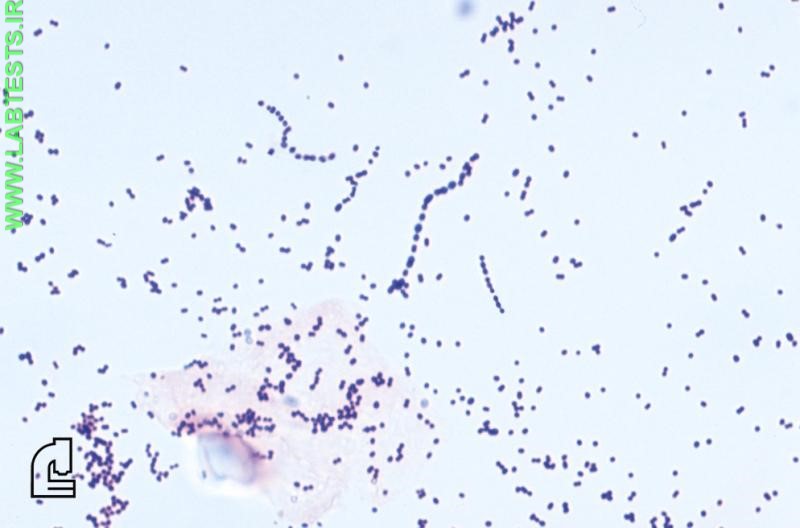

A Gram stain is used, along with a culture of the material from an infected site, to identify the cause of a bacterial infection. The Gram stain provides preliminary results on whether bacteria are present and the general type, such as the shape and whether they are Gram-positive or Gram-negative.

- Whether the bacteria are Gram-positive (purple) or Gram-negative (pink)

- Shape — round (cocci) or rods (bacilli)

- Size, relative quantity, and/or arrangement of the bacteria, if relevant

- Whether there are bacteria present within other cells (intracellular)

- Presence of red blood cells or white blood cells

- Gram-positive cocci—Staphylcoccus aureus (Staph aureus) can cause skin infections and toxic shock syndrome; Streptococcus pneumoniae can cause pneumonia.

The Gram stain involves applying a sample from an infected area or a sample of bacteria grown in culture onto a glass slide. The slide is then treated with a special stain and examined under a microscope by a trained laboratorian. The color and shape of the bacteria help classify which general types of bacteria are present.